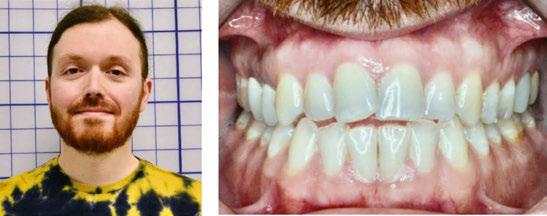

Case progression

At 4 months, the maxillary right side had distalized with appreciable space created between the canine and first premolar (Figure 10). At 9 months, this patient has a wide, attractive smile emerging (Figure 11). We can also appreciate the transverse

This patient’s multiple dental and occlusal issues were resolved solely with Angel Aligner. Both U6s were intruded without needing TAD support or additional mechanics to preclude labial crown torquing. Angel Aligner proved more than adequate in displacing the UR6 vertically while simultaneously distalizing it into Class I (Figure 11). To be able to intrude and distalize simultaneously with no need for TAD-supported anchorage speaks to the exceptional capability of this appliance.

development, arch coordination, and mandibular labial crown torque control. Note how well her tissue responded to the slow, gradual changes with no gingival recession. This is simplicity.